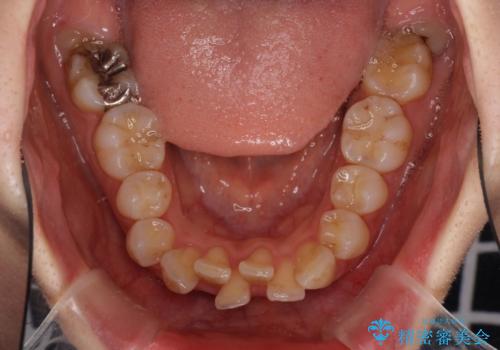

- 上下の出っ歯を気にして来院された患者様です。

口元を積極的に引っ込めるために、上下左右の第一小臼歯を4本抜歯することとしました。

元々ディープバイトのため、スペースを閉じている期間に上下前歯が接触してしまい、治療期間が想定よりも伸びてしまいました。